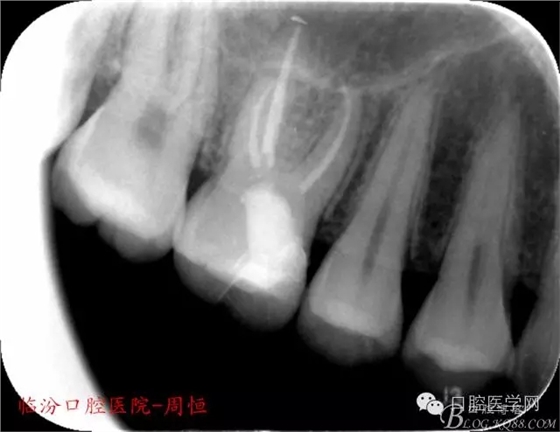

X 示:近中低密度陰影達髓腔,牙根未見異常。

圖1 X示 術(shù)前